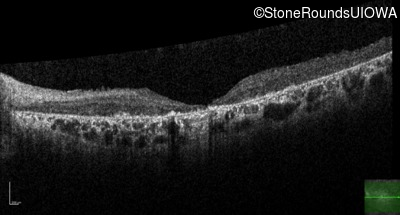

Optical Coherence Tomography - Right - 20/400 sc

Exemplar / OCT Stack